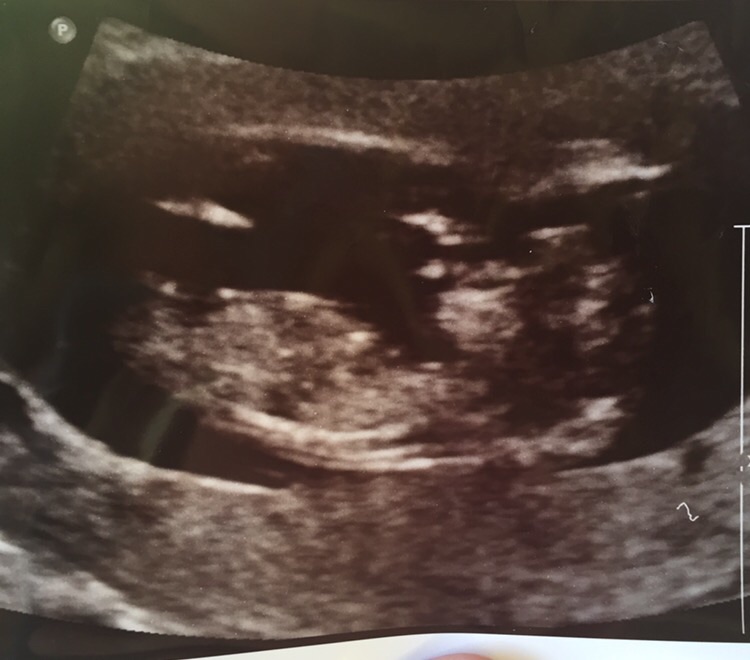

Update !!! Confirmed GIRL

12 weeks + 3 days

We find out on the 24th of December Attachment 34042

We had our scan today & baby was confirmed a GIRL